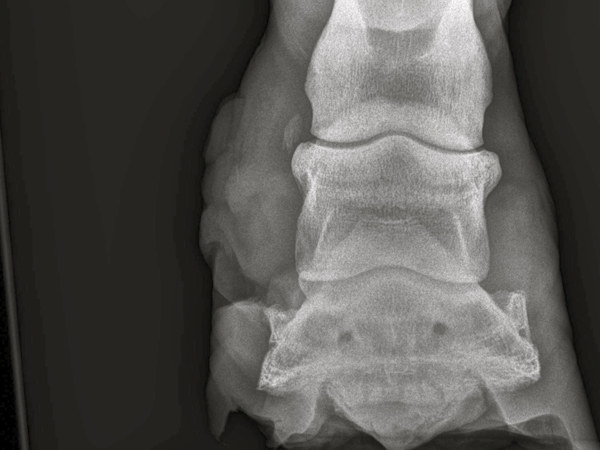

Es gab nur eine Möglichkeit es zu beenden - den Abszessherd zu sanieren, also die eiternde Ursache auszulöschen.Ohne zu zögern machte ich die gesamte Wand entlang des Abszesskanals auf.Es war tatsächlich nicht leer. Danach wurde es reichlich desinfiziert und wieder gut Verbunden. RTG Bilder gemacht. Es hat sich bestätigt das es sich um eine Fistel handelt. Hufknorpel und Co. wurden aber nicht betroffen.